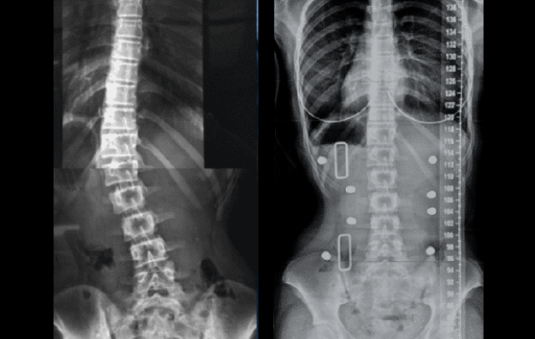

Case – Adolescent Bracing (14 year old female)

Female aged 14 years with a 34° thoracolumbar curve. Reduction of Severe Scoliosis using a 3D Designed Custom Scoliosis Orthosis in a Young Active Female Read more